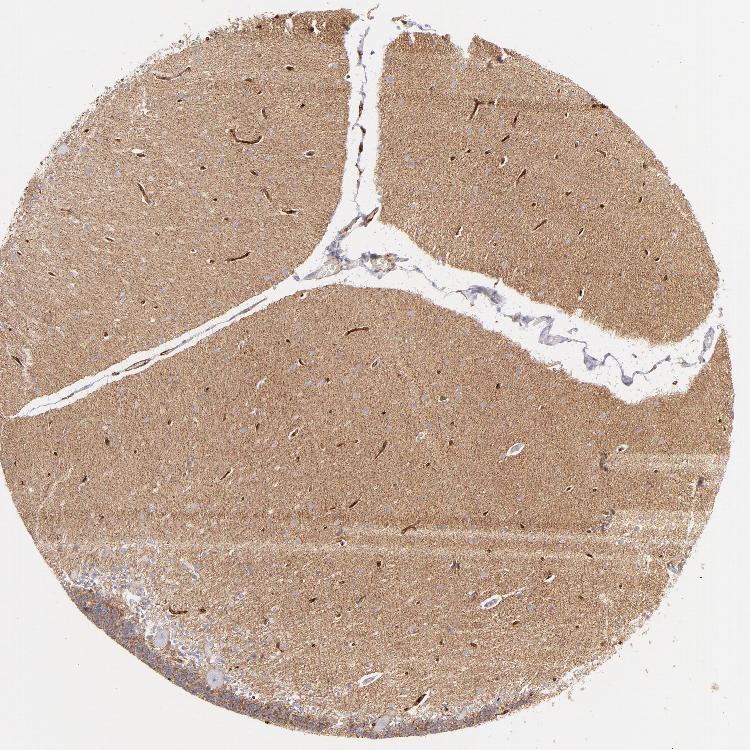

CEREBELLUM - Antibody stainingi

Antibody staining in the annotated cell types in the current human tissue is reported as not detected, low, medium, or high, based on conventional immunohistochemistry profiling in selected tissues. This score is based on the combination of the staining intensity and fraction of stained cells.

Each image is clickable and will lead to virtual microscopy that enables deeper exploration of all samples and also displays staining intensity scores, fraction scores and subcellular localization as well as patient and tissue information for each sample.

Antibody HPA036048Antibody CAB002427

Purkinje cells Not detectedNot detected

Cells in granular layer MediumNot detected

Cells in molecular layer Not detectedNot detected